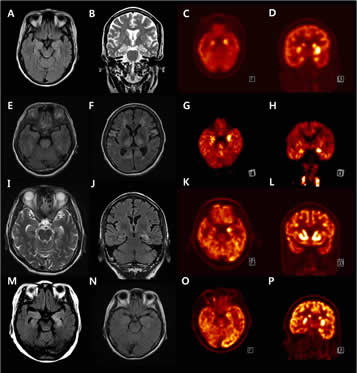

Rationale: Autoimmune synaptic encephalitis (ASE), a rare condition comprising encephalitides associated with autoantibodies against structures of the neuronal synapse, usually accompanies seizure disorder. Leucine-rich glioma inactivated 1 (LGI1), a glycoprotein secreted from presynaptic terminal that regulates presynaptic kv1 channels and post synaptic AMPA receptors, is recently identified as target proteins in ASE, which was formerly attributed to voltage-gated potassium channels. Studies deals with it are small in number. To strengthen our understandings, we presented 11 cases with LGI1 antibodies herein.Methods: Clinical analysis was conducted on patients with suspected ASE. Autoantibodies to NMDAR, LGI1, CASPR2, AMPA1, AMPA2, GABAB-R were checked by indirect immunofluorescence test.Results: Eleven patients with Anti-LGI1 encephalitis were identified. Male to female ratio was 6 to 5 and median age of 61 (range 41-78). All patients presented with seizure, including 6 with brief faciobrachial dystonic seizure (FBDS). 9 patients showed cognitive impairment, mainly memory dysfunction and/or behavioral change. 2 patients had prominent autonomic symptoms, such as orthostatic dizziness, urinary incontinence, and constipation. Ancillary tests such as electroencephalogram, brain magnetic resonance imaging and fluorodeoxyglucose positron emission tomography (FDG-PET) identified medial temporal and/or basal ganglia abnormality in 8 patients. All patients showed symptomatic improvement after immunotherapy.Conclusions: Anti-LGI1 encephalitis is characterized by seizure, cognitive dysfunction, FBDS, basal ganglia hypermetabolism on FDG-PET and hyponatremia. Anti-epileptic therapy is not sufficient to control the symptoms, and early diagnosis and immunotherapy are of importance.